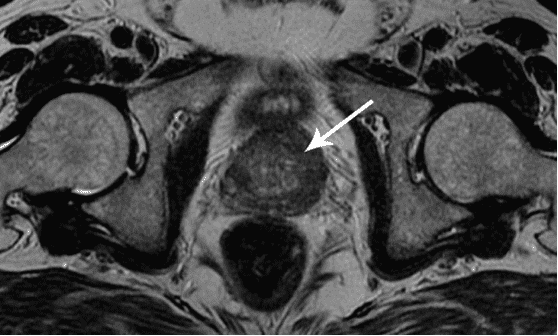

Ich möchte Ihnen ein paar Fotos zeigen, um zu zeigen, was im Urogenitalsystem und anderen Organen eines Mannes vor sich geht, der keinen Sex hat.

So sieht eine Entzündung der Prostata aus, die durch Stagnation der Spermien verursacht wird (wenn die Hoden nicht geleert werden). Eine anhaltende Entzündung führt zuerst zu einem Prostataadenom und dann zu Krebs. Dies ist eine unvermeidliche Folge von Prostatitis, daher wird es als "Krankheit der älteren Generation" bezeichnet.